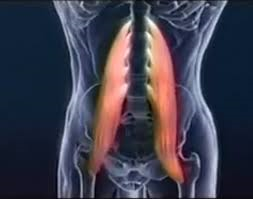

- Ejercicios flexibilizadores para mantener la movilidad de los segmentos lumbo-pelvicos.

- Tratamiento del musculo psoas, muy importante para el proceso de encajamiento del bebé.